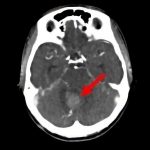

断層撮影

手術前1

手術前2